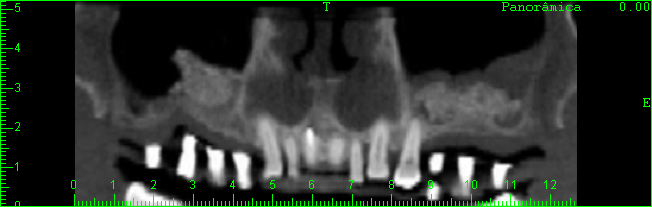

TOMOGRAFIA COMPUTADORIZADA APÓS A REALIZAÇÃO DO ENXERTO ÓSSEO DE BANCO DE OSSO